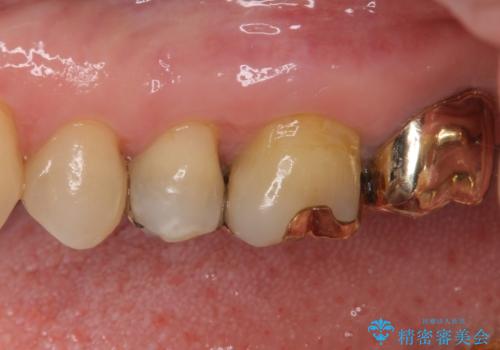

外れてしまった銀歯 セラミックインレーで自然な仕上がりに

- 奥歯の銀歯が外れてしまったため、セラミック治療を希望された患者様です。

セラミックインレーによる修復治療を実施しました。

正面から見える場所であったため、セラミックインレーで自然な口元にすることができました。